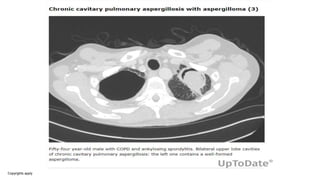

Chronic cavitary pulmonary aspergillosis

• CCPA, formerly called complex aspergilloma, usually shows

multiple cavities, which may or may not contain an

aspergilloma, in association with pulmonary and systemic

symptoms and raised inflammatory markers, over at least 3

months of observation.

• Radiographic imaging reveals one or more thick- or thin-walled cavities

that often have irregular walls and intracavitary material; aspergillomas

may develop within the cavities as the disease progresses. The upper

lobes are most commonly affected. As the disease progresses, new

cavities develop or existing cavities expand, and they may coalesce or

perforate into the pleural space.

• Infiltrates are common surrounding the cavities. The thickness of cavity

walls represents the inflammatory activity of the disease as well as

possible adjacent fibrosis. For lesions close to the pleura, pleural

thickening is very common. Concomitant findings include bronchiectasis,

nodules, ground glass changes, tree-in-bud changes, and organizing

pneumonia.

Imaging showing chronic cavitary pulmonary aspergillosis showing an axial view with a) lung and b) mediastinal

windows at the level of the right upper lobe.

David W. Denning et al. Eur Respir J 2016;47:45-68

©2016 by European Respiratory Society

• #18 Imaging showing chronic cavitary pulmonary aspergillosis showing an axial view with a) lung and b) mediastinal windows at the level of the right upper lobe. Multiple cavities are visible with a fungus ball lying within the largest one. The wall of the cavities cannot be distinguished from the thickened pleura or the neighbouring alveolar consolidation. The extra pleural fat is hyperattenuated (white arrows). *: the dilated oesophagus should not be confused with a cavity.